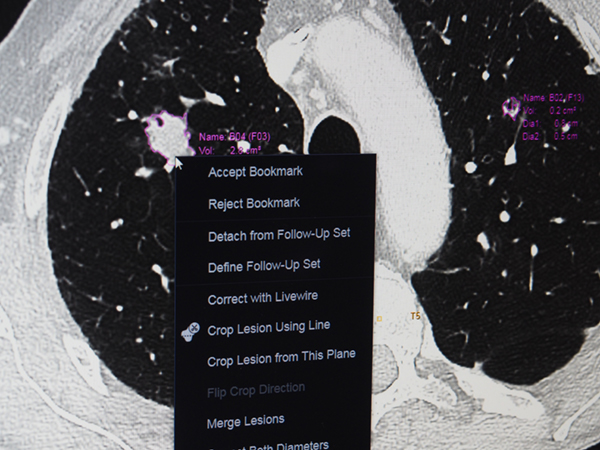

また,同社ではすでにゼブラ・メディカル・ビジョン社のAIベースの解析アルゴリズの搭載をアナウンスしているが,今回の展示では,独自開発のAI技術(部位や病変を自動認識する診断補助機能など)をCCPに搭載し,患者選択を行うワークリストから,ビューワ,そしてレポートまでの読影ワークフローに適用して,放射線科医の診断業務をサポートする新たな機能について紹介した(独自開発のAIはW.I.P.)。

自社開発のAI技術で病変を自動認識して計測値などを表示(W.I.P.)